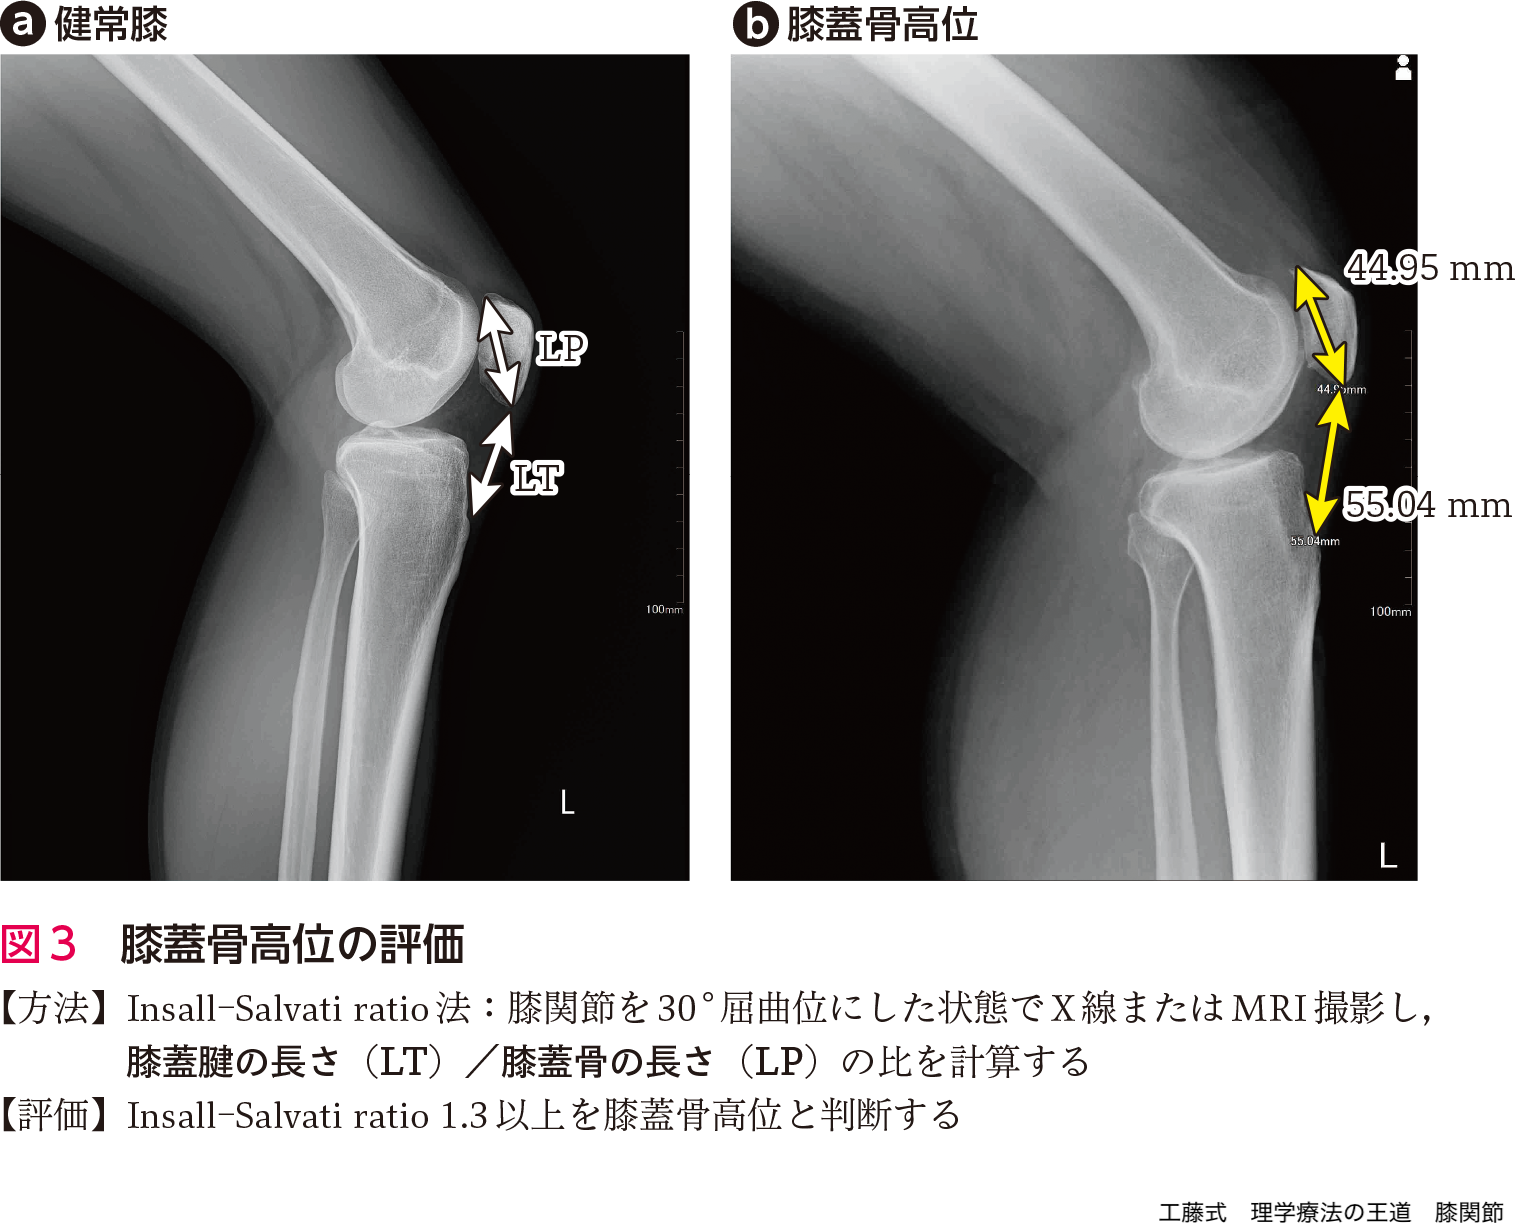

膝蓋大腿関節の低形成は膝蓋大腿関節症と関連する.そのためX線の軸写像にて大腿骨内/外側顆の大きさを評価する(図2).また膝蓋骨高位も膝蓋大腿関節症の発生に関与することが知られている.そのため,Insall-Salvati ratioを用いて膝蓋骨高位の評価を行う(図3).通常では,1.3以上を膝蓋骨高位と判断するが,膝蓋大腿関節の関節症変化の発生という観点では1.14がcut off pointになる6).